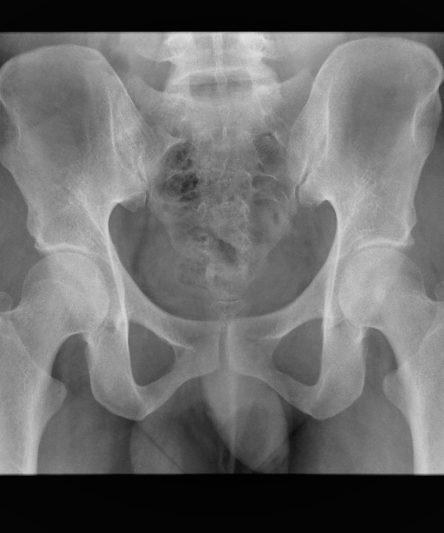

Microskan with Ultra high frequency can take the Lateral Lumbar Spine image of a 90 kg Patient with the correct image receptor